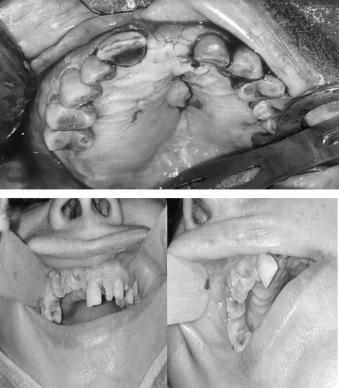

Covid-19 chủ yếu ảnh hưởng đến hệ hô hấp tuy nhiên, một số ít bệnh nhân cũng xuất hiện biến chứng răng hàm mặt gồm cả hoại tử xương.

Mới đây, một nhóm các nhà khoa học Hy Lạp đã công bố nghiên cứu về 12 ca bị hoại tử xương hàm sau nhiễm Covid-19 từ 37 tới 68 tuổi. Bảy người trong số đó là nữ. Tất cả các trường hợp đều đồng nhiễm một bệnh khác và được kê đơn thuốc kháng viêm corticoid khi điều trị Covid-19.

Thời gian bắt đầu xuất hiện các triệu chứng hoại tử xương trung bình là 5-7 tuần tính từ ngày có kết quả xét nghiệm PCR âm tính. Bệnh nhân được phẫu thuật khử trùng và dùng kháng sinh trước và sau mổ tối thiểu 3 tuần. Tất cả các bệnh nhân được theo dõi trong ít nhất 2 tháng, không có ca tái phát.

Theo BMC, chứng hoại tử xương hàm hiện có thể coi là một trong những biến chứng răng hàm miệng tiềm ẩn hậu Covid-19.

Điều đặc biệt là tất cả các trường hợp có sự liên hệ tiềm ẩn giữa hoại tử xương hàm và Covid-19 xuất hiện triệu chứng ở hàm trên. Điều này có thể do niêm mạc mũi và xoang hàm trên gần nhau. Người ta suy đoán viêm tủy xương do viêm xoang là điểm khởi đầu cho tình trạng nghiêm trọng này vì SARS-CoV-2 là bệnh nhiễm trùng đường hô hấp.

Tình trạng hoại tử xương hàm xảy ra ở những bệnh nhân đã hồi phục sau nhiễm SARS-CoV-2 đang là một mối quan tâm dù số lượng chưa nhiều. Các bệnh nhân có vấn đề sức khỏe tiềm ẩn và những người được kê đơn corticoid được đánh giá có nguy cơ đáng kể.